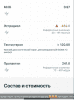

тебя с метана-то не порвало еще?Тест энантат. 500мг, метан 210мг, Нандролон 350мг в неделю.

Масса поперла и апетит зверский. Все препы Паркер